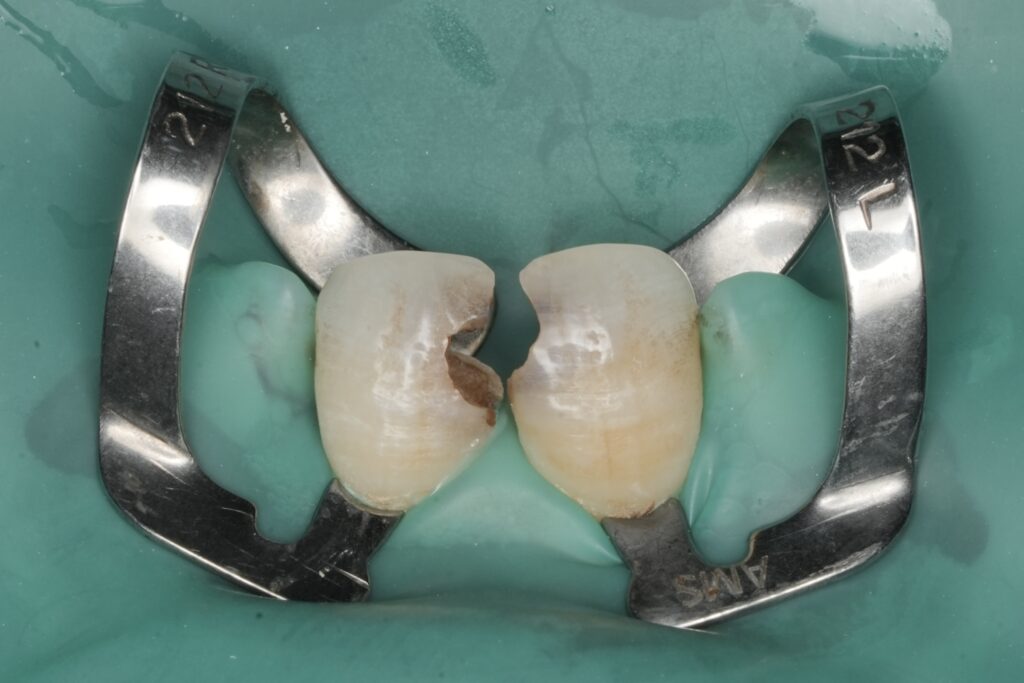

4) Conservative caries removal and margin evaluation

Remove unsupported enamel and compromised tissue conservatively. If a deep cervical margin is present, either:

- manage with careful matrix/wedge adaptation, or

- consider margin elevation if indicated (only when isolation and seal are achievable).

The priority is a clean, sealable margin.